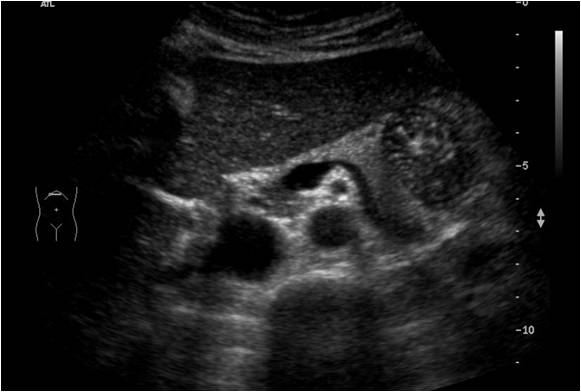

Se encuentra situado según la imagen anterior, posterior al Hígado y anterior a la aorta, pero lo que de verdad nos sirve de referencia para encontrar el órgano es una imagen en forma de renacuajo, anecoica y que en la imagen siguiente está silueteada en blanco.

Esta es la referencia más importante para encontrar el páncreas cuando lo estudiemos, encontrar esta estructura anecoica, que pasa justo posterior al órgano que lo acompaña y lo marca, que tiene forma de renacuajo y que es la Esplénica en su parte más delgada y la Porta en su parte más gruesa. Es sin duda la estructura que va a ayudarte, la aliada principal para encontrar ecográficamente el Páncreas.